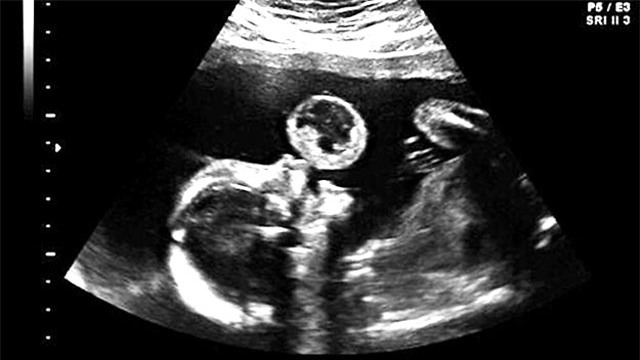

Nhìn thấy con lớn mạnh mỗi ngày, Tammy và chồng vui mừng khôn xiết. Đến tuần thai thứ 17, chị vẫn đi siêu âm theo chỉ định và khá bất ngờ khi nhìn lên màn hình, chị thấy con dường như đang “thổi bong bóng” rất đáng yêu. Tuy nhiên, đến khi bác sĩ công bố kết quả, chị như không tin vào tai mình, tay chân rụng rời hết cả.

Đến tuần thai thứ 17, chị vẫn đi siêu âm theo chỉ định và khá bất ngờ khi nhìn lên màn hình, chị thấy con dường như đang "thổi bong bóng" rất đáng yêu (Ảnh: Internet)

Theo các bác sĩ chẩn đoán, thai nhi đã mắc phải khối u quái Teratoma rất hiếm gặp, một dạng u phát triển từ tế bào mầm. Sau khi xem xét, bác sĩ đưa ra hai lời đề nghị: bỏ thai hoặc phẫu thuật nội soi cắt bỏ khối u. Tuy nhiên, nếu chọn phẫu thuật thì tỉ lệ thành công là khá thấp. Vậy là Tammy bắt buộc phải lựa chọn bỏ thai hoặc phẫu thuật. "Họ bảo khối u phát triển rất nhanh và phải can thiệp sớm", chị Tammy nhớ lại.